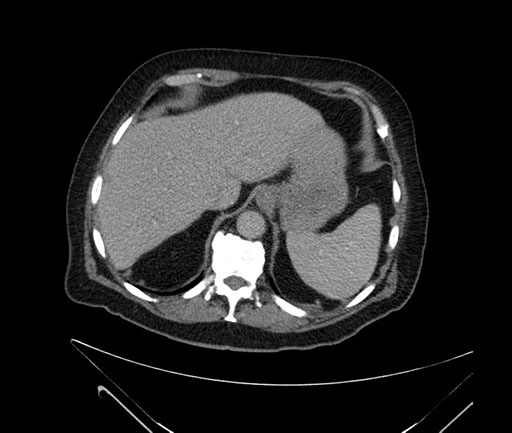

Imaging Analysis

Look through the patient's CT scan to identify any areas of concern for the necessary procedure.

Based on your CT findings, which issue(s) would give reason for "planned slowing down moment(s)" in this case?